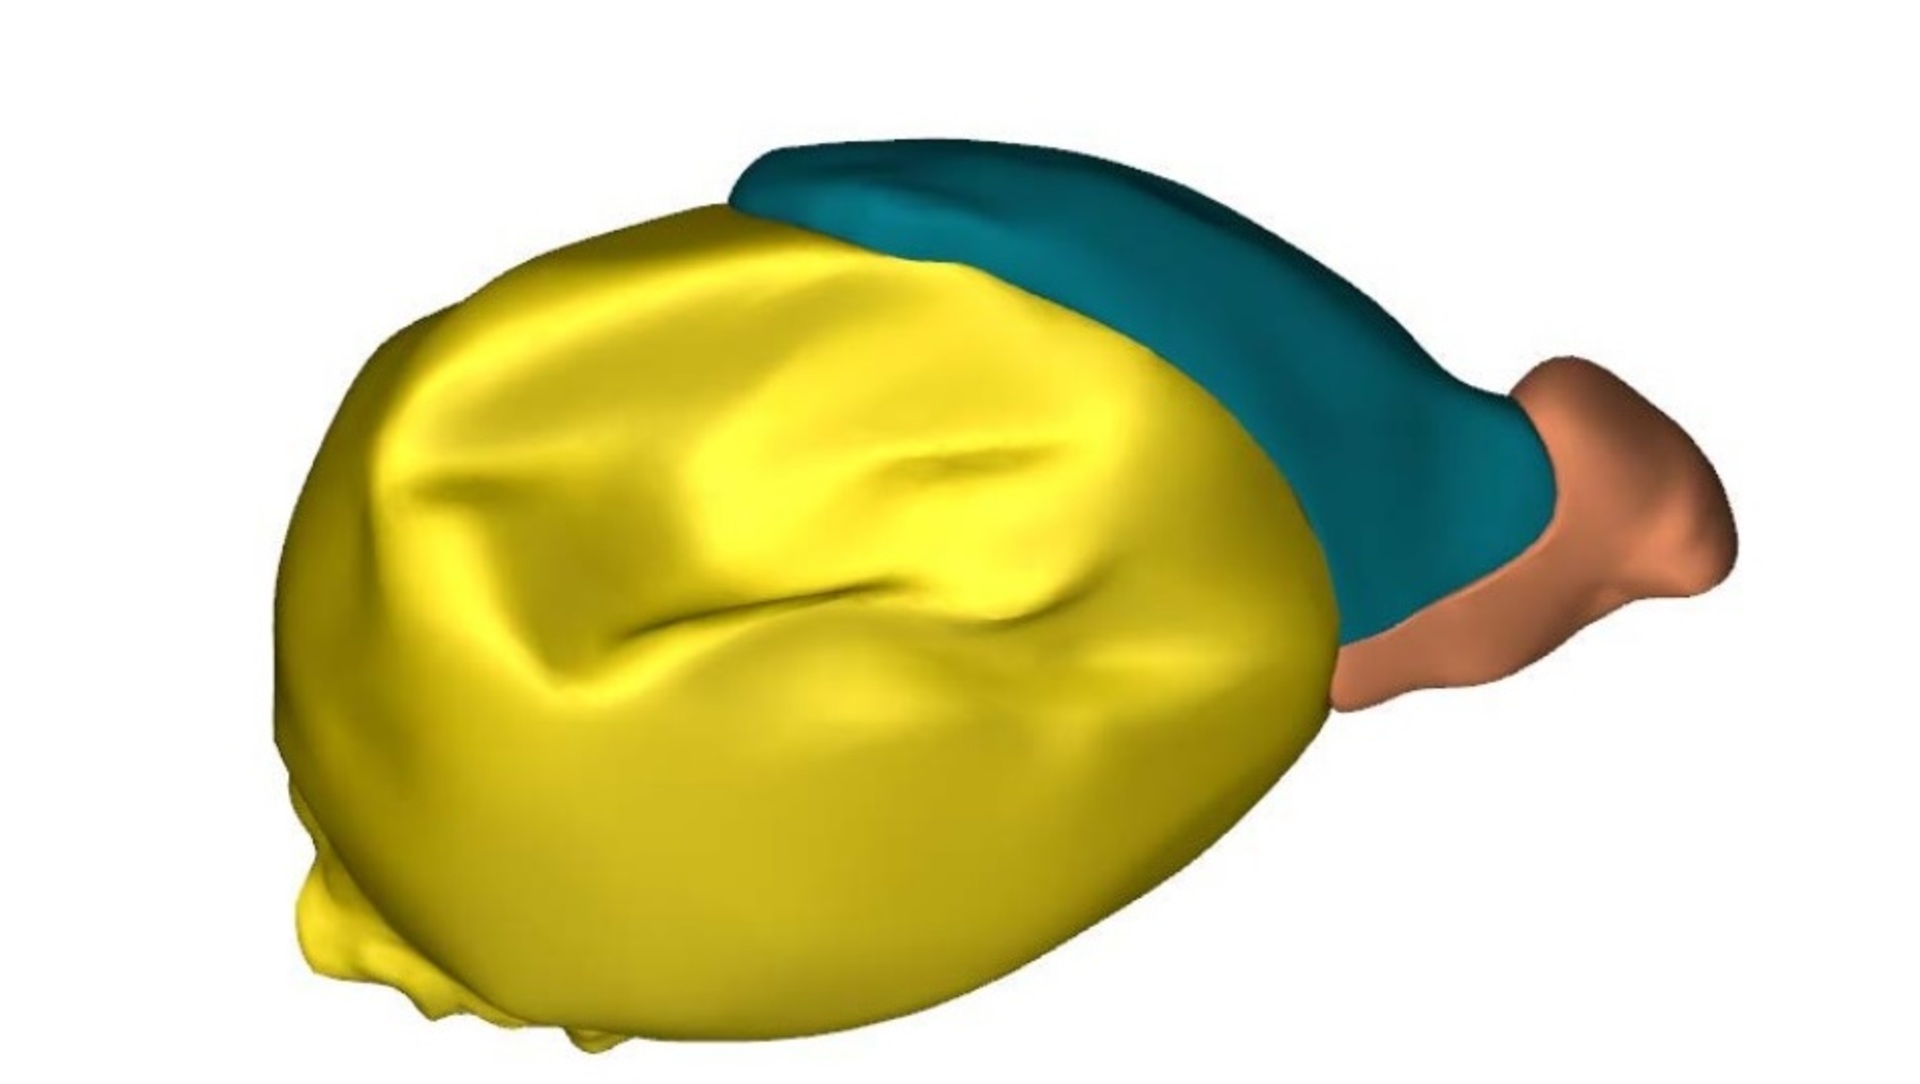

Ученые Академического медицинского центра в Амстердаме идентифицировали и промаркировала 150 структур и органов тела эмбрионов, после чего реконструировали их трехмерные компьютерные модели.

Атлас позволяет рассмотреть как эмбрион в целом, так и его отдельные структуры, органы и системы.